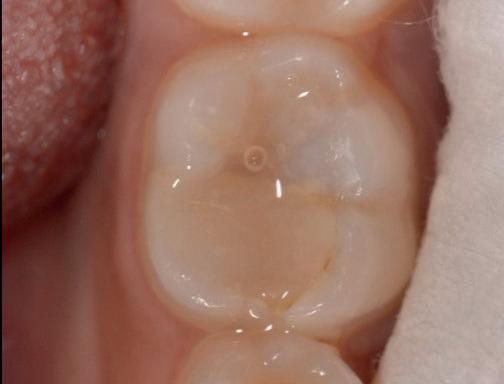

Predictable management of a deep carious lesion, page 27